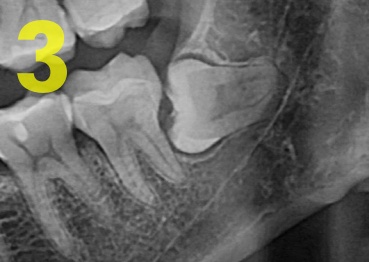

③ 완전 매복 : 치조골에 2/3 이상 묻혀있을때 (사진3)

1에서 3으로 갈수록 난이도가 올라가고 발치 비용도 비싸져요.